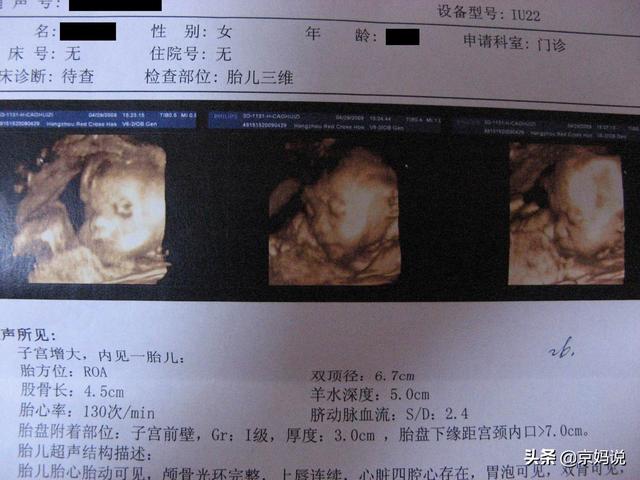

J'ai lu beaucoup de réponses de médecins, mais aucune ne mentionne laLes conseils en matière d'échographie qui comptent le plus pour les femmes enceintes,En effet, il n'y a pas moins de quatre échographies à effectuer tout au long de la grossesse, et de nombreuses futures mamans sont désorientées lorsqu'elles reçoivent leur ordonnance d'échographieTant que le médecin n'explique pas spécifiquement le problème, les mères enceintes l'ignorent, de toute façon, le fœtus est normal.

Chaque échographie permet non seulement d'observer le développement du fœtus (longueur, poids, etc.), mais aussi de détecter la probabilité que le fœtus souffre de malformations à un moment donné.Il est important que la mère enceinte puisse lire la feuille d'échographie.Lorsque vous recevrez la liste des échographies, jetez-y d'abord un coup d'œil, et si vous ne comprenez pas ou n'êtes pas sûr d'un certain indicateur, ou si vous constatez que votre valeur s'écarte de la valeur normale, vous pouvez en parler à votre médecin pour vous assurer que les indicateurs sont normaux.

Comment lire le bulletin d'échographie pendant la grossesse ?

Pour lire un bulletin d'échographie, il est important de comprendre les tests courants et leurs acronymes :

Diamètre bipariétal (BPD), diamètre occipitofrontal (OFD), longueur du fémur (FL), longueur de l'humérus (HL), circonférence de la tête (HC), circonférence abdominale (AC), rapport de débit sanguin du cordon ombilical (A/B), position du fœtus (LOA) et liquide amniotique (AMN).

Comme le fœtus se développe de manière dynamique, chaque échographie présentera des données différentes, et comme ces données sont trop nombreuses, Jingma n'entrera pas dans les détails ici, choisissant les plus importantes, que j'ai expliquées en détail dans mes questions-réponses précédentes.

1. diamètre bipariétal

se référer à"La partie la plus longue de la tête du fœtus, de gauche à droite.Également connu sous le nom de"Le grand diamètre transversal de la tête du fœtus.。

Rôle :Principalement pourEstimation du poids du fœtus et de son état de développementFin de grossesseDétermination de la présence d'une asymétrie céphalopelvienne,S'il est possible d'avoir un accouchement réussi.

enceinte juilletLe diamètre bipariétal de la tête du fœtus était alors de 7,24-7,65 cm.à terme (gestation)En cas d'accouchement, elle peut aller jusqu'à9,3 cm ou plusMon fils avait une grosse tête à l'époque et est né avec un diamètre bipariétal de 9,9 cm et a failli ne pas sortir du ventre de sa mère.

2. diamètre frontal occipital

se référer à"Distance entre la racine du nez du fœtus et la branche occipitale.également connu sous le nom de"Le sentier de l'avant et de l'arrière"La valeur de la partie la plus longue de la tête du fœtus, d'avant en arrière, est également calculée.

Rôle :Ces données sont généralement utilisées pourDétermination du développement du fœtus et de la semaine de gestation。

3. la longueur du fémur

se référer à"La longueur de la cuisse du fœtus.Également connu sous le nom de"Longs os de la cuisse".Il s'agit deLa partie la plus longue du corps du fœtusLa valeur du

Rôle :Généralement utilisé en conjonction avec le diamètre bipariétalEstimation du poids du fœtus。

Sa valeur normale diffère de 2 à 3 cm de la valeur du diamètre bipariétal du mois de grossesse correspondant, par exemple si le diamètre bipariétal est de 9,3 cm, la longueur du fémur est de 7,3 cm ; si le diamètre bipariétal est de 8,9 cm, la longueur du fémur est de 6,9 cm.

4. longueur de l'humérus

se référer à"La longueur de l'os supérieur du bras du fœtus.。

Rôle :C'est aussi pourEstimation du poids du fœtus Le.

5. le périmètre crânien

se référer à"La longueur de la tête du fœtus en une semaine.Cet indicateur est également mesuré par le médecin lors de l'examen physique du bébé après la naissance.

Rôle :À titre de comparaison, il est généralement utilisé pourConfirmation du développement du fœtus。

6. la circonférence abdominale

se référer à"La longueur de l'estomac du fœtus en une semaine.Également connu sous le nom de"Circonférence abdominale".

Rôle :Généralement avec d'autres valeursEstimation de l'état de développement du fœtus。

7. taux de circulation du sang du cordon ombilical

Il s'agit du "flux sanguin à travers le cordon ombilical", qui constitue le seul canal pour les échanges gazeux, l'apport de nutriments et l'élimination des produits métaboliques entre la mère et le fœtus.

correspond à l'anglais -ity, -ism, -izationLa modification de l'hémodynamique de l'ombilic peutReflète certains changements pathologiques dans le placenta, le fœtus et la mère, ainsi que certains facteurs de grossesse à haut risque.

8. position fœtale

se référer à"La position et l'attitude du fœtus dans l'utérus.Le plus courant est leLa position normale du fœtus est occipitofrontale ou céphalique.

Rôle :principalement utilisé pourDécider du mode de livraisonSi la position du fœtus est correcte, l'accouchement peut être normal, alors que la plupart des médecins recommanderont une césarienne si le fœtus n'est pas dans la bonne position.

9. AMN-羊水

C'est la valeur du liquide amniotique.Principalement utilisé pour déterminer la quantité de liquide amniotique.Il existe deux façons de déterminer la valeur du liquide amniotique :

MVP:se référer àProfondeur verticale maximale du bassin de moutons,2-8 cm, c'est normalSi l'eau dépasse 8 cm, il y a trop de liquide amniotique, et si elle est inférieure à 2 cm, il n'y a pas assez de liquide amniotique.

AFL :se référer àl'indice de liquide amniotique (ILA)L'indice de liquide amniotique (AFI) est obtenu en additionnant la profondeur du liquide amniotique dans les quatre zones : supérieure, inférieure, gauche et droite, centrées sur l'ombilic de la femme enceinte.La valeur normale de l'indice du liquide amniotique en fin de grossesse est de 8 à 20 cm.Plus de 20 cm, c'est trop de liquide amniotique et moins de 8 cm, c'est trop peu de liquide amniotique.

10. autres indicateurs

Sur la tête du fœtus :Un contour intact est considéré comme normal, les défauts et les déformations sont considérés comme anormaux, et l'absence de déplacement de la ligne médiane du cerveau et d'hydrocéphalie est considérée comme normale.

Sur le cœur du fœtus :Le rythme cardiaque normal du fœtus est de120-16 battements/minuteLa présence et la force sont normales, l'absence et la faiblesse sont anormales.

Mouvements du fœtus : la présence et la force sont normales, l'absence ou la faiblesse sont anormales.Il peut aussi s'agir d'un fœtus endormi, à analyser en conjonction avec d'autres éléments.

A propos du placenta :placentaireL'épaisseur normale est de 2,5 à 5 cmLe placenta est situé sur la paroi utérine et est classé en trois degrés de maturité : le degré 0 indique que le placenta n'est pas encore mature ; le degré I correspond au stade précoce de la maturité placentaire avec des échos uniformes ; le degré II indique que le placenta est proche de la maturité ; le degré III indique que le placenta est mature et que plus la date prévue de l'accouchement se rapproche, plus le placenta devient mature et plus les échos deviennent irréguliers.

A propos du dos :La continuité de la colonne vertébrale du fœtus est normale, mais la perte est anormale et peut être malformée.

L'échographie peut également montrer clairement diverses images en coupe des organes du fœtus et des organes environnants, ce qui permet au médecin d'obtenir davantage d'informations, d'exclure les lésions dangereuses et de permettre aux futures mamans de traverser la période de grossesse en toute confiance et d'accoucher en douceur. J'espère que ces informations aideront les futures mamans et je vous souhaite une bonne grossesse.